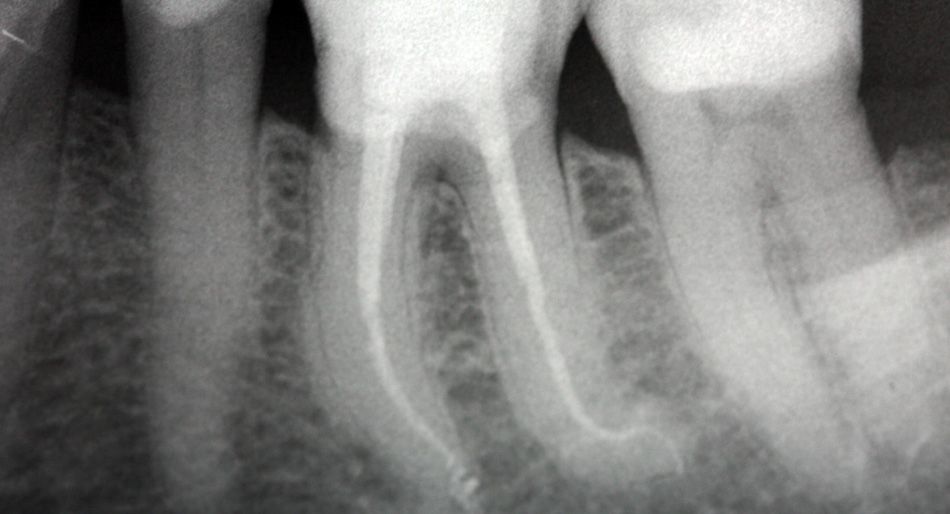

Radiografia dentale di un dente; il trattamento canalare è visibile con contorni netti, su uno sfondo scuro.

Lo stato dell’arte in endodonzia è ormai universalmente riconosciuto essere la microscopia. Terapie che in passato risultavano impossibili diventano oggi di routine lavorando ad alti ingrandimenti.

È così possibile curare con successo ascessi, granulomi e infezioni dentarie, grazie anche all’utilizzo di strumenti avanzati come il rilevatore elettronico di apice, gli strumenti NiTi e il micromotore ad induzione.

Le tecniche microchirurgiche permettono inoltre di recuperare denti altrimenti destinati all’estrazione o di intervenire su precedenti fallimenti terapeutici tramite apicectomie, rimozione di strumenti fratturati nelle radici e sigillature di perforazioni radicolari.